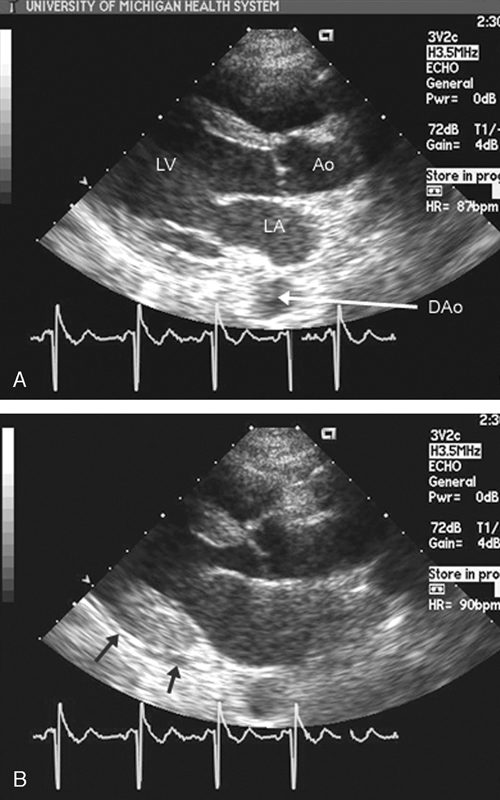

فحوصات تشخيصية لبعض امراض القلب والشرايين التاجية